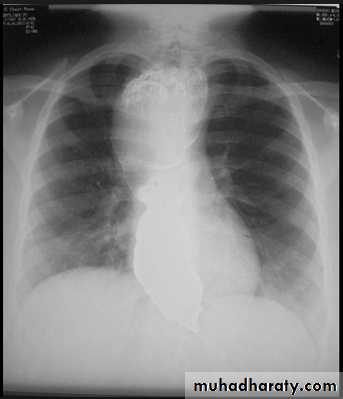

Massive pleural effusion with mediastinal shift to the left.

(A) Chest radiograph(B) CT coronal reconstruction. A massive effusion displaces the mediastinum to the left. CT shows the important pleural effusion together with the enhanced atelectatic left lung.

Note also the depression of the right hemidiaphragm (arrows).